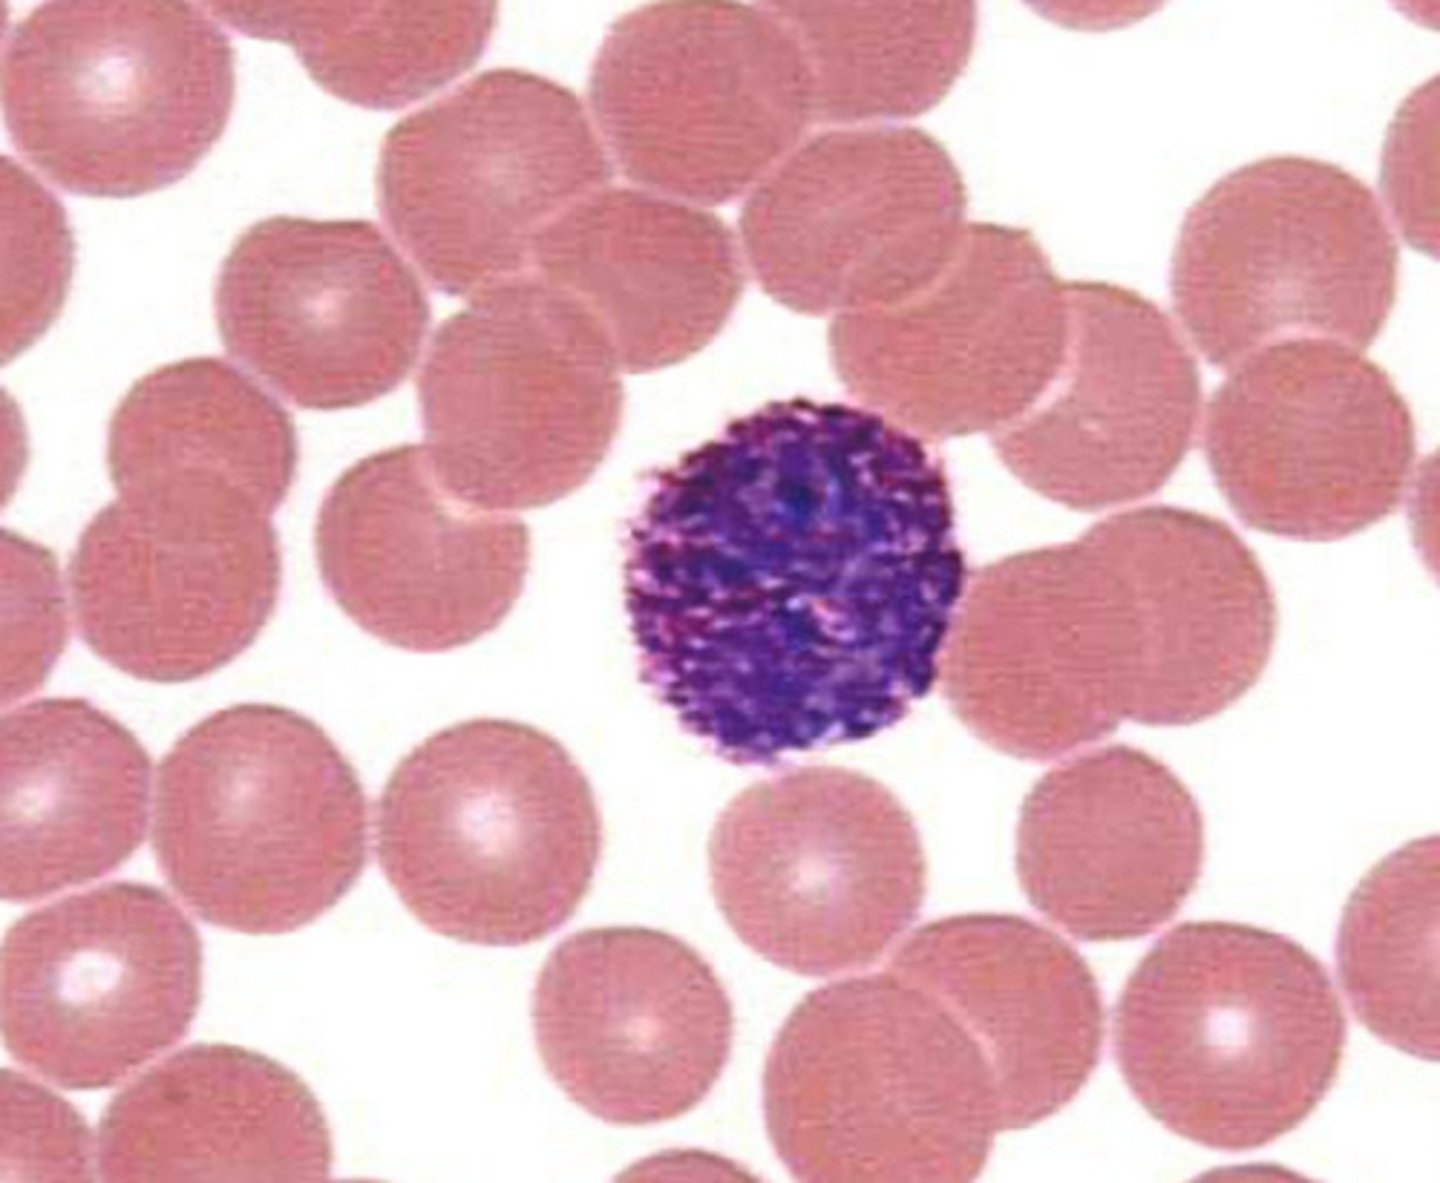

Lymphocytes

Structure: Has a large, dark purple nucleus that takes up most of the cell volume

Function: B cells make antibodies, T cells fight off viral infections, NK cells